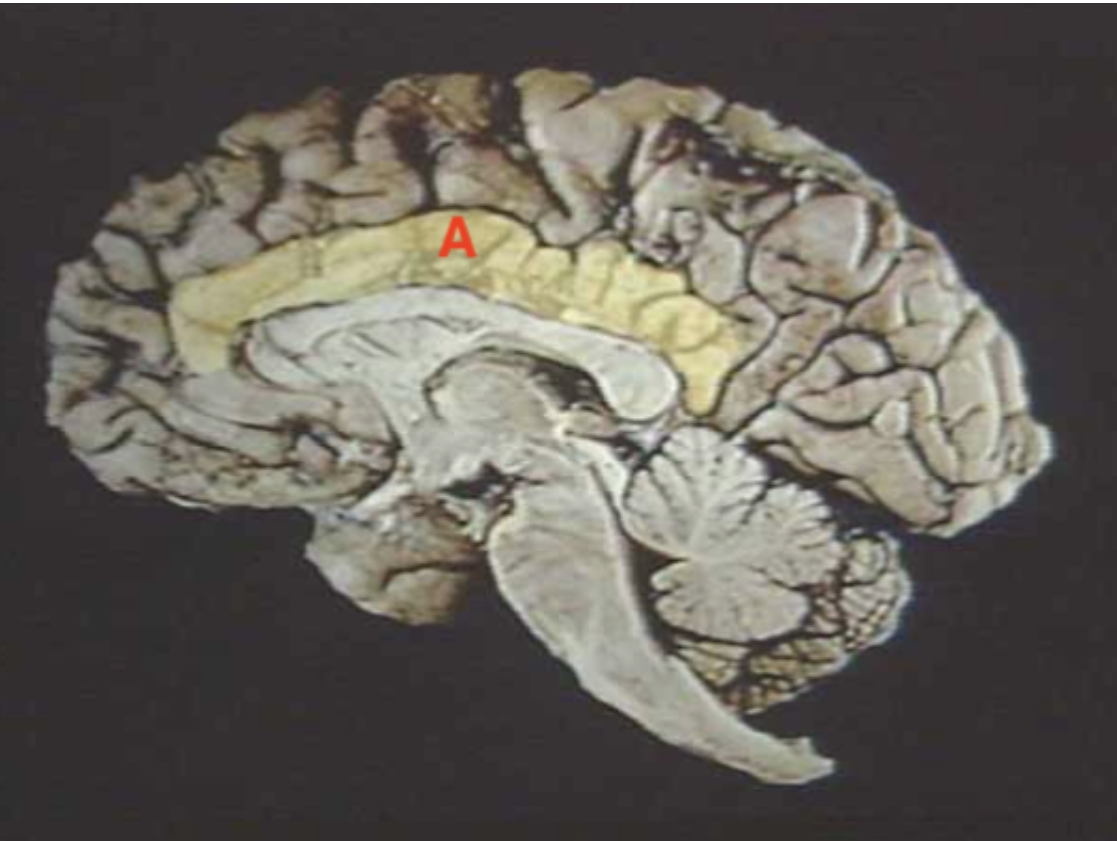

A

Corpus Callosum